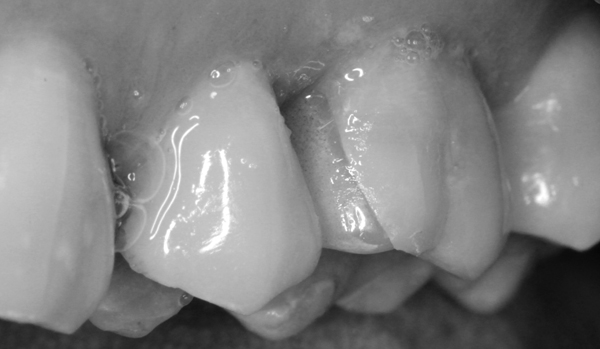

Schwarzweiß-Filter zur Demonstration der Helligkeitsunterschiede:

Detail Schwarzweiß: